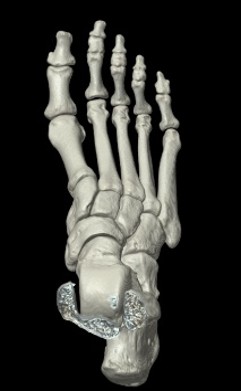

CT撮影室

X線を使って体を輪切りにした画像を構成します。

当院では80列マルチスライスCTが稼働しており、数秒の息止めで胸部から骨盤まで撮影することができ

ます。また被ばくを低減させる機能も搭載されています。